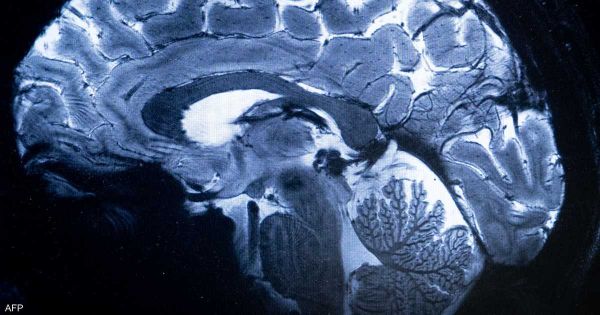

دراسة: مخ الانسان يغتسل أثناء النوم

على مدار عقود طويلة، ظل العلماء يفكرون في مشكلة أساسية، وهي كيف يتخلص مخ الانسان من النفايات التي